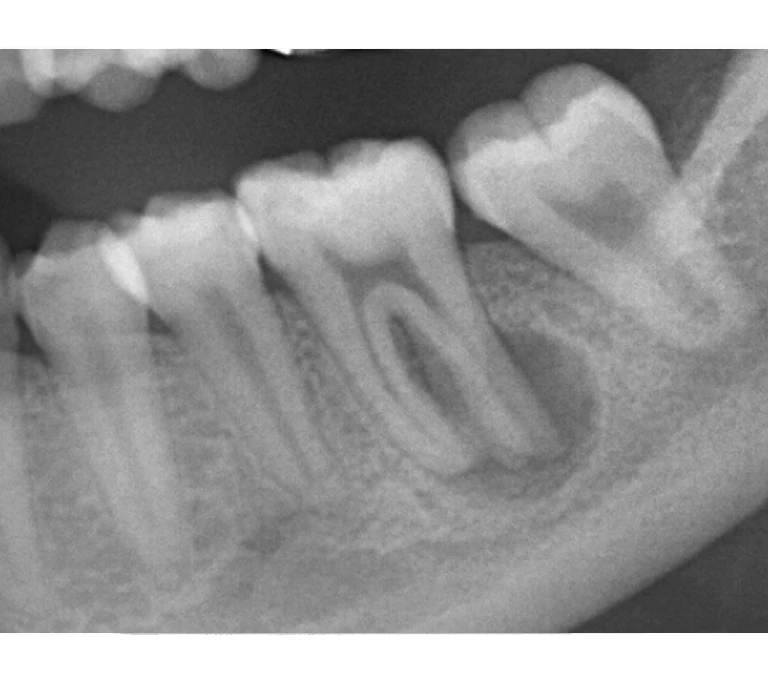

治療前

治療後

| 主訴 | 右下歯ぐきの腫れ。 他院で抜歯と言われ、セカンドオピニオン希望でご来院。 |

|---|---|

| 治療期間 | 1か月 |

| 治療費 | 約2万円 |

| 治療内容 | ラバーダム、マイクロスコープ下にて根管治療を施術。歯肉腫脹と疼痛は消失し補綴物を作製し治療終了。治療後のレントゲン写真は2年後のものです。 |

| 治療のリスク | マイクロスコープやCTを使用し、可能な限り精密な根管治療を行っていますが、歯根の形態や病変の大きさ、過去の治療履歴などにより、治癒が得られない場合があります。 また、治療後に再感染や歯根破折が生じることもあり、その場合は再治療や抜歯が必要となることがあります。 治療結果には個人差があり、すべての症例で同様の経過を保証するものではありません。 |